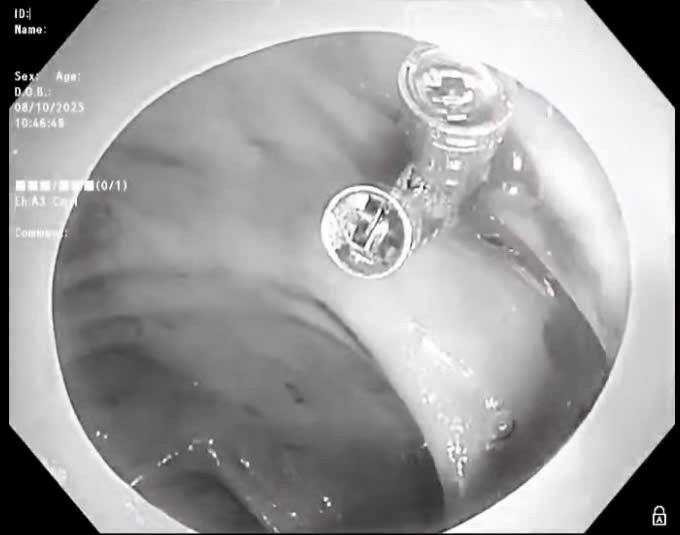

| PGS.TS Lương Ngọc Khuê, Phó Trưởng Tiểu ban Điều trị, Ban Chỉ đạo quốc gia phòng chống dịch bệnh COVID-19 hội chẩn trực tuyến với các bệnh viện. |